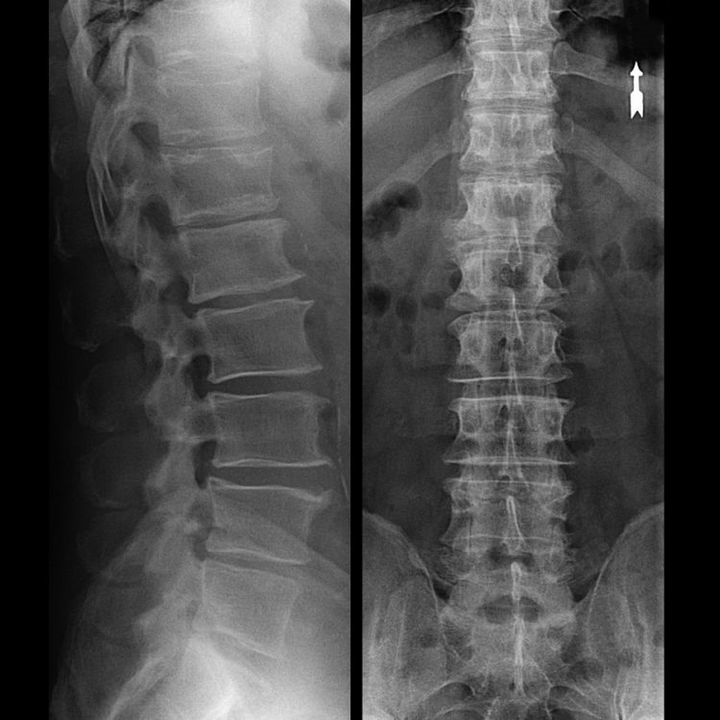

Eine „Röntgenaufnahme“ der Halswirbelsäule und selbst bei Funktionstests für Beugung und Streckung zeigt keinen Knorpel, da deren Gewebe Röntgenstrahlen durchlässt. Trotzdem kann man anhand der Lage der Wirbel allgemeine Rückschlüsse auf die Höhe der Bandscheiben, die allgemeine Aufrichtung der physiologischen Krümmung des Halses – Lordose – sowie auf das Vorhandensein von Randwucherungen an den Wirbeln mit längerer Reizung ihrer Oberflächen durch brüchige und dehydrierte Bandscheiben ziehen. Funktionstests können die Diagnose einer Instabilität der Halswirbelsäule bestätigen.

Da die Bandscheiben selbst nur mittels CT oder MRT sichtbar sind, sind Magnetresonanztomographie und Röntgen-Computertomographie angezeigt, um den inneren Aufbau von Knorpel und Formationen wie Vorwölbungen und Hernien abzuklären. Somit wird mit Hilfe dieser Methoden eine genaue Diagnose gestellt und das Tomographieergebnis ist ein Hinweis und sogar ein aktueller Leitfaden für die chirurgische Behandlung eines Leistenbruchs in der neurochirurgischen Abteilung.